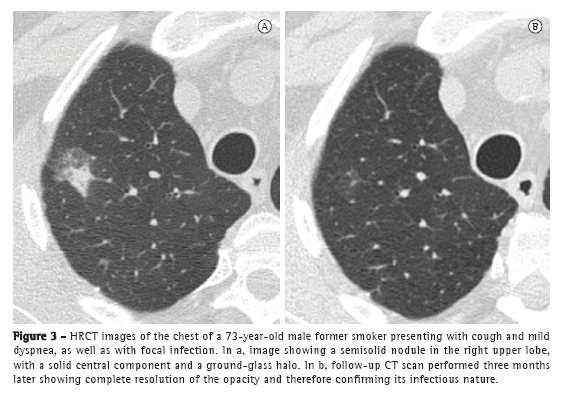

Ground-glass opacities raise a number of differential diagnoses, which range from benign diseases, such as focal fibrosis and lesions of an infectious nature, to pre-malignant opacities, such as atypical adenomatous hyperplasia (AAH), and malignant lesions, such as BAC and adenocarcinoma with a bronchioloalveolar component.(14) The current WHO classification for lung tumors defines AAH as a pre-malignant lesion-a precursor to BAC-with particular morphological and molecular characteristics, the most common CT finding in AAH being a pulmonary nodule with ground-glass attenuation.(1) Nakata et al. studied CT characteristics that could aid in the differential diagnosis of BAC and AAH and reported that AAH is generally < 1.0 cm and presents as pure ground-glass opacities, whereas BAC is at least 1.0 cm and can show solid components.(15) In daily practice, the follow-up evaluation of focal ground-glass opacities is crucial. Although most benign lesions tend to become smaller or disappear in three months, pre-malignant and malignant lesions can remain unchanged or grow (Figure 3).(16)